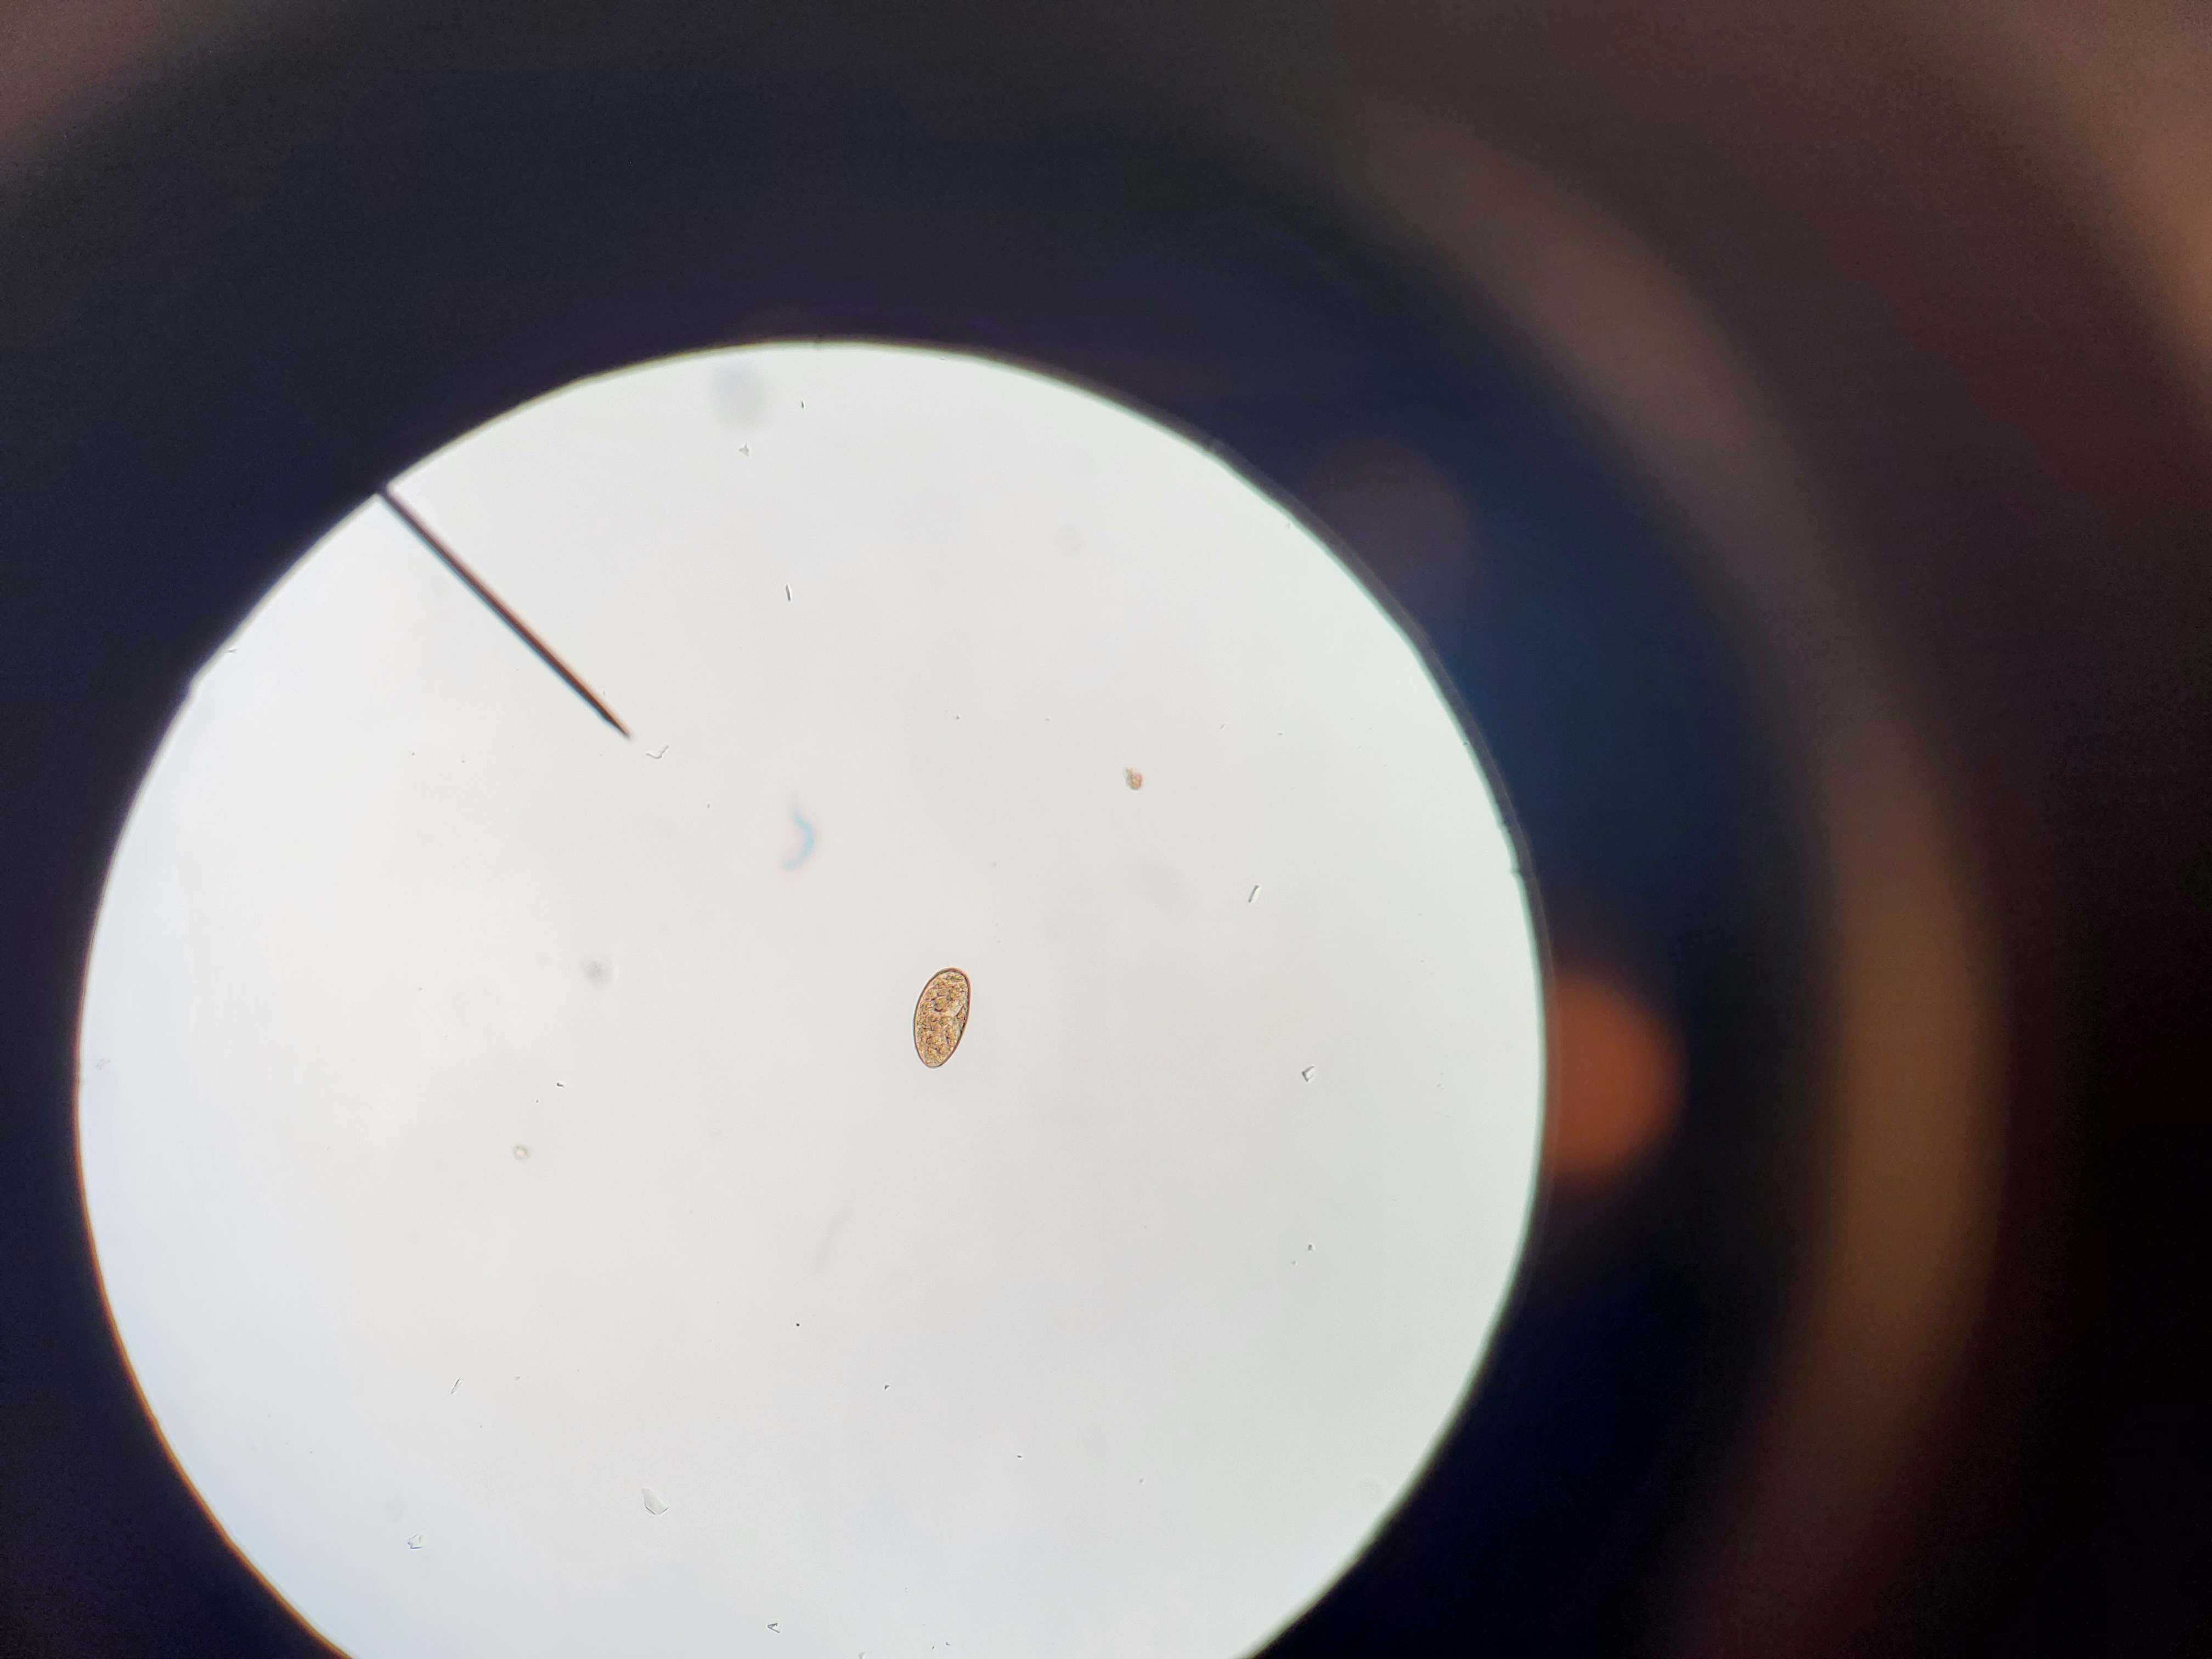

Schistoma mansoni

Stage: Egg

Sample type: Fecal